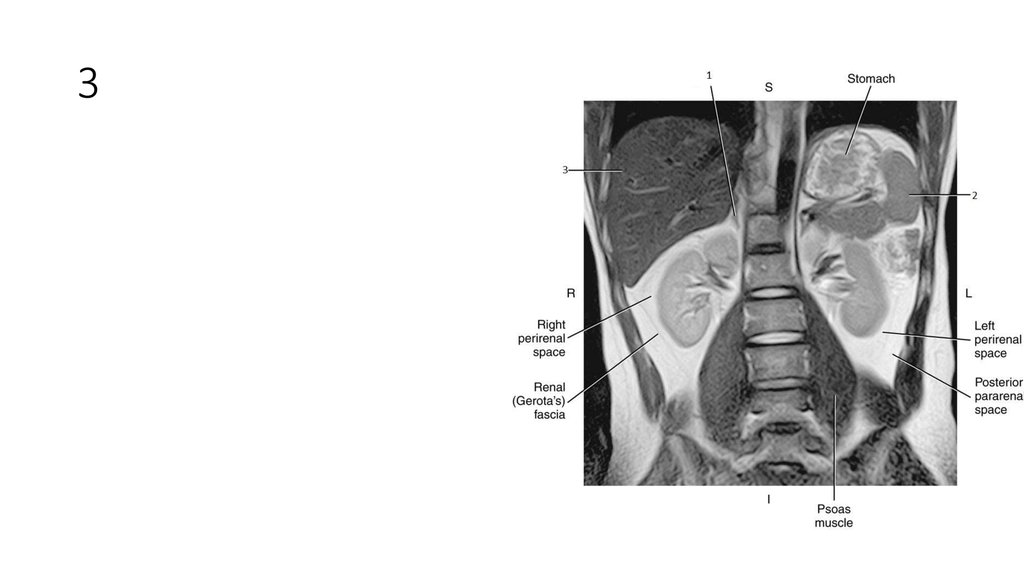

2. 1

• Liver

4. 2

• Spleen

6. 3

• Aorta

7. 3

8. 4

• Inferior Vena Cava (IVC)

9. 4